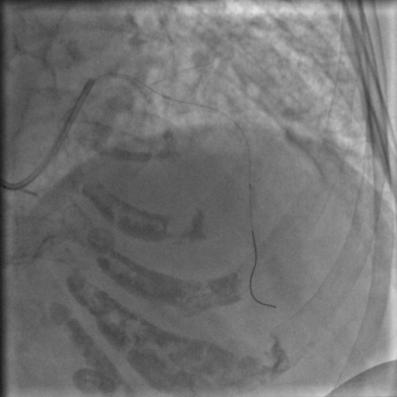

常规消毒、铺巾,再穿刺、放鞘管、送入造影导管、造影,一切顺利,造影结果如下:

图2

图3

图4

比我们想象中的要好,前降支中段闭塞,第一、第二对角支都还在,回旋支、右冠都还好,可以稍微松一口气。